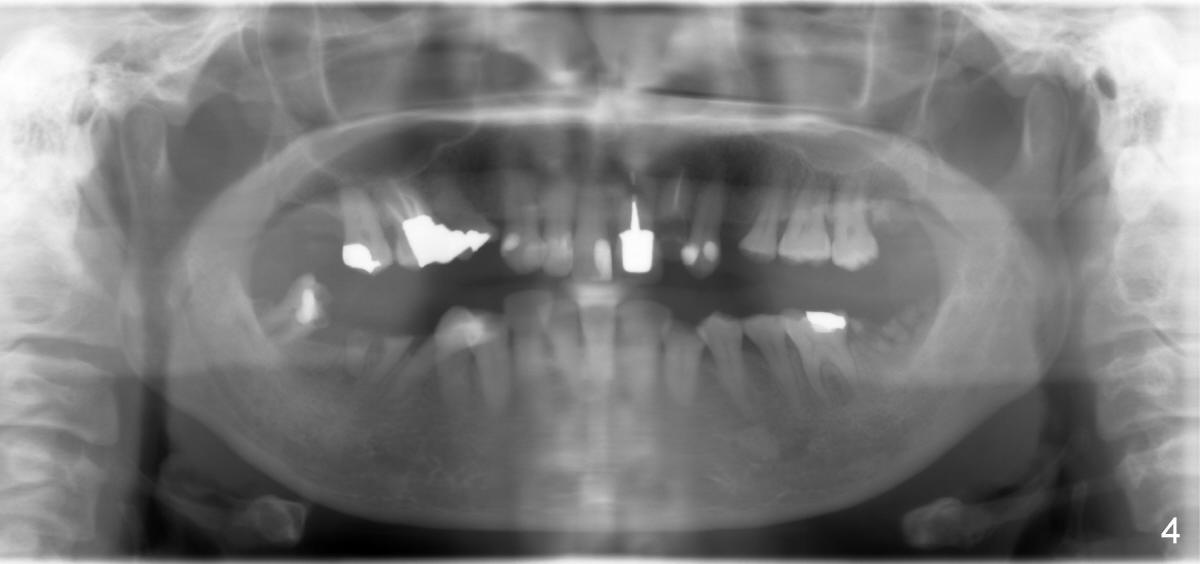

陈女士,五十来岁,牙齿问题多,左上侧切牙龋齿严重(图一,二*),终于牙冠断了(图三),很奇怪牙根不见了。虽然她缺牙不少(图四),她只要求做一个前牙(侧切牙)植牙。不过间隙太小(图三*),无法植牙,我们必须先做牙齿矫正。这可为难病人,因为她胆子特别小。

如果心细的话,你可能发现左上第一双尖牙缺失(图二,四),我们能否利用这个间隙,将尖牙往远中牵拉,为侧切牙创造空间,那里植牙就没问题了?不妨再次研究图三,四,你可能找到初步答案,或者你需要什么进一步资料?下次见。